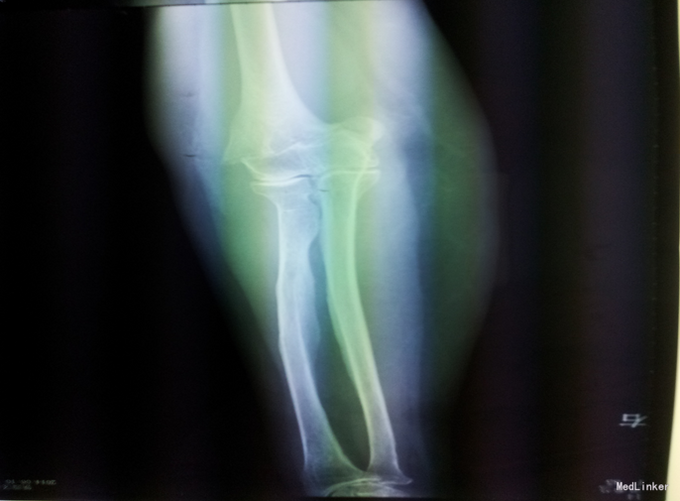

主诉:右肘关节疼痛活动受限5小时。现病史:5小时前,在家中摔倒,意识清醒,先后右膝、左上肢着地,自觉右上肢疼痛,伴活动受限。后就诊于铁西区中心医院,行右肘关节正侧位DR提示肱骨骨折,左膝关节正侧位提示未见异常,未予治疗,现为求进一步诊治来我院就诊

辅助检查:右上肢及手部肿胀,前臂绷带悬吊中,右肘关节及周围压痛,可触及骨擦音,骨擦感。左膝关节处肿胀。四肢感觉正常,肌张力正常。右侧握力、右腕背伸4级,余四肢肌力正常。右桡动脉搏动良好。

诊断:右肱骨骨折 治疗:切开复位内固定术